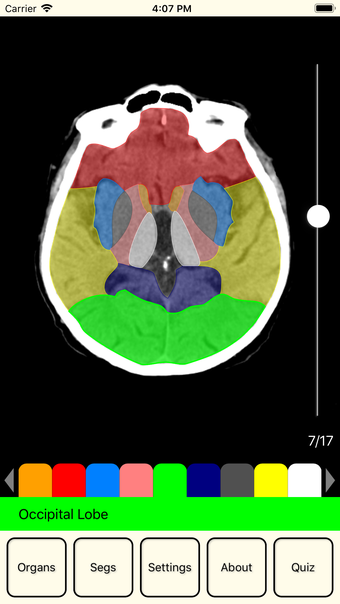

Die Benutzeroberfläche ermöglicht es, durch Bildschnitte des Organs zu blättern, indem der Daumen auf der rechten Seite des Hauptbildes geschoben wird. Durch Antippen des Hauptbildes können Benutzer ein Segment auswählen und dessen Namen am unteren Rand des Bildschirms anzeigen. Die App bietet zudem die Möglichkeit, die Sichtbarkeit der Segmente anzupassen und sich in einem Quiz selbst zu testen.